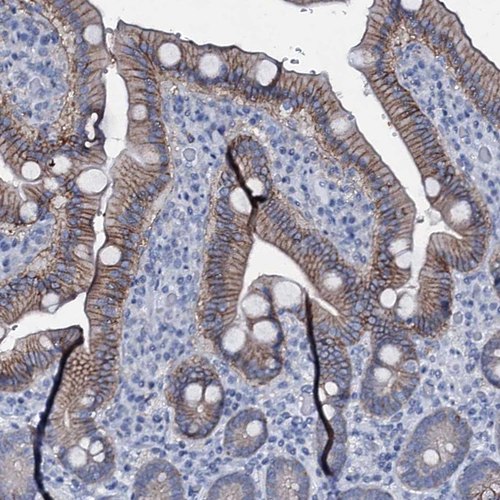

Immunohistochemistry analysis in human duodenum and liver tissues using HPA035857 antibody. Corresponding SLC4A7 RNA-seq data are presented for the same tissues.